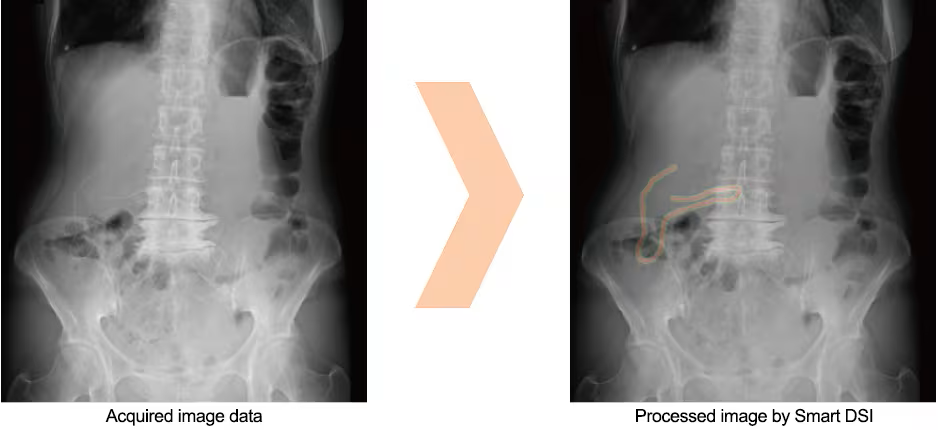

Smart DSI: Retained object confirmation support image processing OPTION

Developed with AI technology, Smart DSI aids the detection of objects retained in the body by enhancing regions of the image that potentially show surgical needles, gauze with radiopaque threads, and other foreign objects .*1)

Display images processed by Smart DSI *2)

Processed image by Smart DSI

- *1) The AI (artificial intelligence) technology used in Smart DSI is not a self-guided interactive learning-type AI.

- *2) Do not rely solely on the imaging processing capabilities of Smart DSI when determining if foreign objects are retained in the patient. Use visual confirmation of images, gauze counts, and other methods in reaching a final judgement.